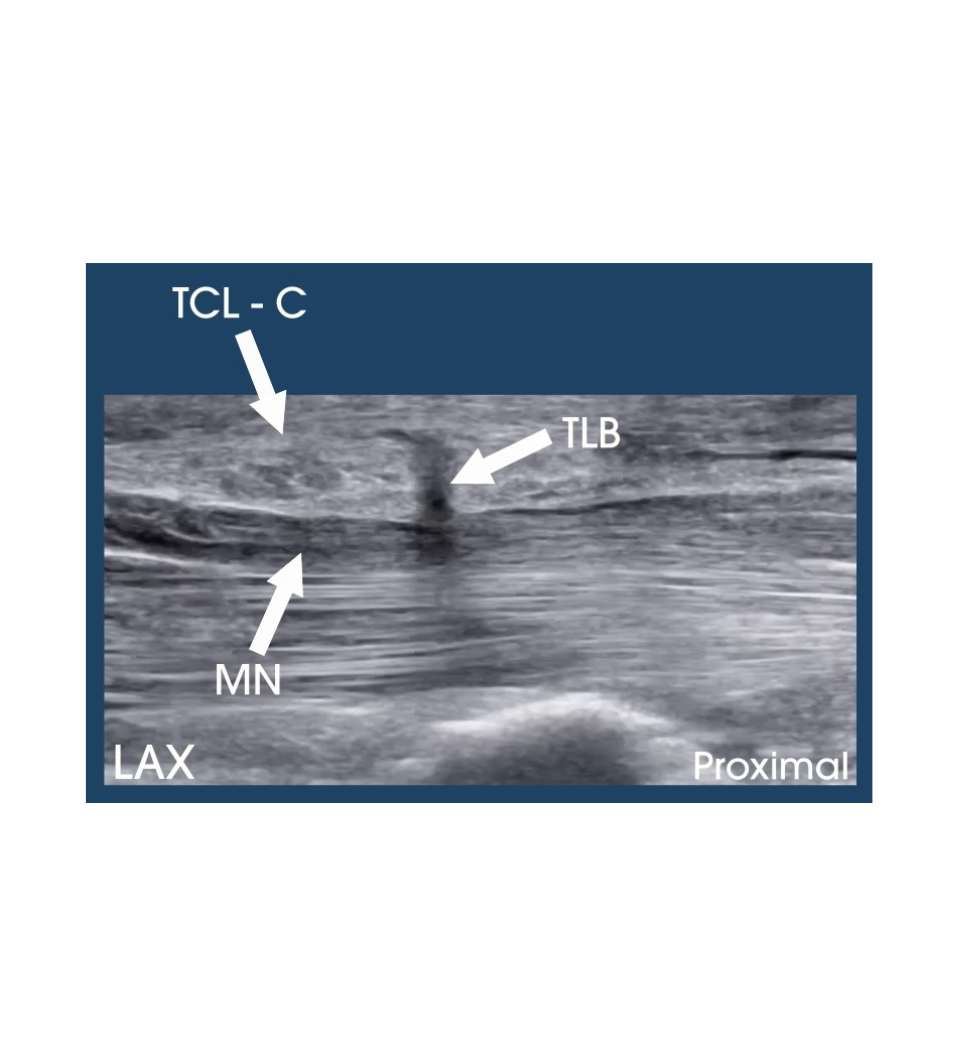

Community Posts Transligamentous Branch of the Median Nerve

Transligamentous Branch of the Median Nerve

Posted November 13, 2025 by Doug Hoffman